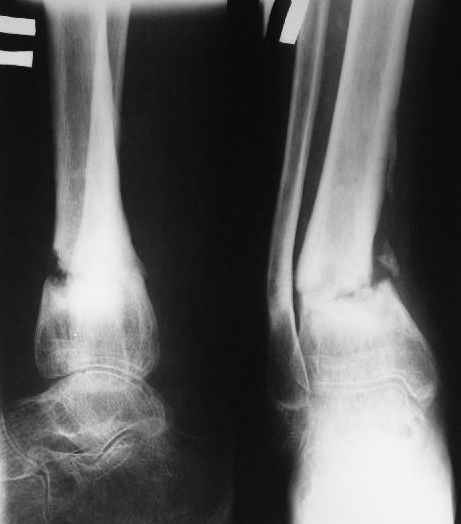

Ребенок 12 лет, поступил после падения с высоты примерно 2,5м.

Перелом костей н\3 правой голени со смещением. Перелом большеберцовой кости можно охарактеризовать как компрессионно-оскольчатый.

В январе 2005: варусная деформация н\3 голени, болевой с-м, комбинированная контрактура г\стопного сустава, нейропатия м\берцового нерва сохраняется слабость разгибания 1 пальца.

Операции: 1 Клиновидная резекция на вершине деформации м\берцовой кости.

2 Тугоподвижный ложный сустав н\3 б\берцовой кости. Рубцы выполняющие пространство между отломками, канал проксимального отломка иссечены.

Одномоментное устранение деформации, остеосинтез Г-образной пластиной.

Пластика по Хахутову.